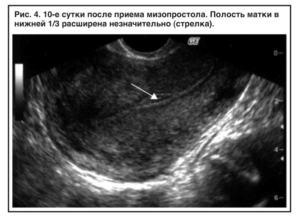

Гинеколог выявляет мягкую консистенцию органа при осмотре. Подтверждают развившийся негативный процесс клинические и биохимические анализы мочи и крови, трансвагинальное УЗИ (ультразвуковое исследование).

Проводится визуальный осмотр шейки матки и пальпация. Внутренний зев ее будет расширен, плодный остаток в наличии. УЗИ определит его объем и локализацию, а также общее состояние репродуктивных органов. Биохимический анализ крови расскажет о функционировании органов и систем пациентки.

При неполном аборте беременность больше не подтверждается различными тестами, поэтому примерно через неделю после отторжения плодного яйца необходимо сделать УЗИ, чтобы удостовериться, что в матке нет остатков эмбриональной ткани. Если остатки плодного яйца после медикаментозного прерывания беременности обнаружены, следует вовремя начать лечение.

Что делать? Лучше этот вопрос заранее обговорить с врачом. По стандартным рекомендациям УЗ-исследование после аборта выполняют на 10-14 день, но если это сделать через 5-7 дней, то есть возможность вовремя заметить признаки неполного аборта и назначить лекарственные средства.

Но так или иначе, лучше сделать УЗИ матки. Платно можно и без направления врача. А по его результатам будет понятно — нужно ли лечение, в том числе хирургическое.

Через 2–3 дня женщина вновь должна посетить врача. Гинеколог осмотрит пациентку, оценит ее состояние. Будет проведено УЗИ, результат которого покажет эффективность проведенной процедуры. Если выкидыш при помощи медикаментозных средств не произошел, женщине понадобится чистка. Беременность после фармаборта сохранять нельзя.

При появлении первых симптомов, вызывающих опасение, женщина должна обратиться в больницу. Основными методами диагностики состояния являются гинекологический осмотр и УЗИ.